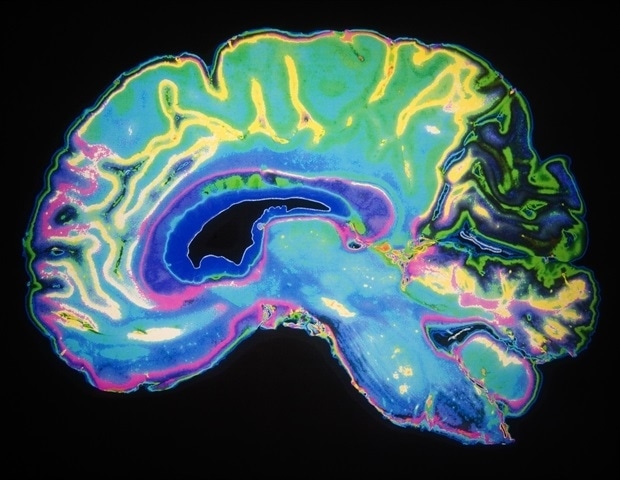

Recent research by a team led by Maarten Kole at the Netherlands Institute for Neuroscience has unveiled critical insights into the role of myelin in the rapid transmission of signals in the brain. The study, published in March 2025 in the journal Nature Communications, highlights how the absence of this protective layer around nerve cells impacts communication between the cerebral cortex and the thalamus, a key relay station in the brain.

Myelin acts as insulation for nerve fibers, enabling swift signal transmission across long distances. The study focused on mice to understand the implications of myelin loss, particularly in the corticothalamic loop, which is crucial for processing sensory information. When mice use their whiskers to explore their surroundings, this loop facilitates effective communication between the brain’s outer layer and the thalamus. The findings emphasize the significance of these loops not only in mice but also in human cognitive functions.